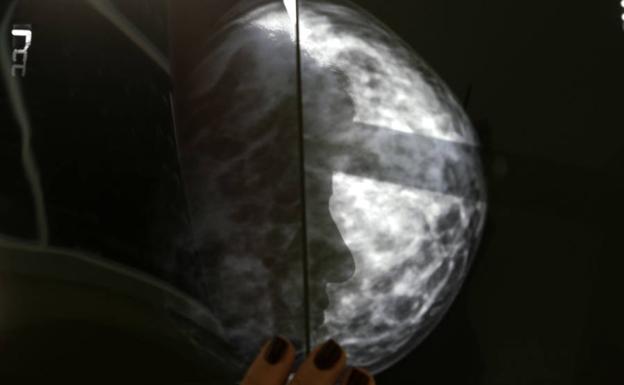

Científicos españoles diseñan una técnica pionera para combatir el cáncer desde el interior del tumor

Si funcionase los efectos secundarios de la quimioterapia se reducirían enormemente, aunque aún está lejos de aplicarse en seres humanos